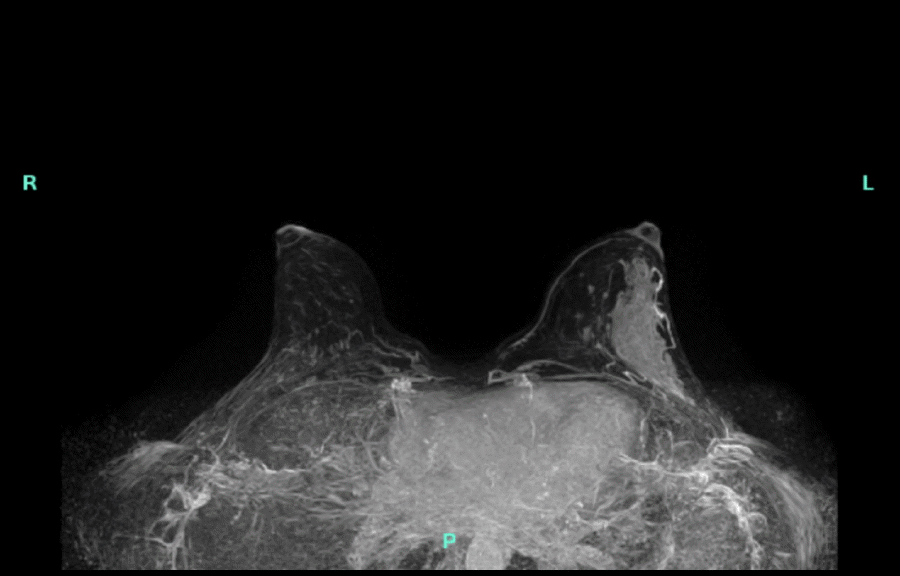

A 32-year-old female with a family history of a paternal grandmother diagnosed with breast cancer at age 65, followed by colon cancer at age 80, reported a palpable left breast mass for almost a year. Diagnostic imaging revealed a 5.2 × 1.1 × 4.3 cm heterogeneous hypoechoic mass at the left 3-to-4 o'clock position, which was suspicious for malignancy (Figure 1 and Figure 2). Subsequent bilateral breast MRI revealed a left breast 7.2 × 2.0 × 4.4 cm avid non-mass enhancement with a wedge-shaped distribution abutting the chest wall, highly suggestive of malignancy and mildly prominent left axillary lymph nodes (Figure 3).

Figure 3. MRI Demonstrating Non-mass Enhancement in Left Breast, Suspicious for Malignancy. Published with Permission

Upon completion of neoadjuvant chemotherapy, a follow-up bilateral breast MRI showed a complete radiographic response with no residual enhancement in the area of biopsy-proven carcinoma. Although she preferred to undergo bilateral nipple-sparing mastectomy with reconstruction due to her family history and dense breasts, she agreed to undergo staged surgery due to hospital limitations on surgical procedures during the COVID-19 pandemic. Thus, she underwent a wire localized lumpectomy and sentinel lymph node biopsy (SLNB) utilizing a dual tracer technique with radioactive technetium and methylene blue dye, revealing a complete pathologic response to neoadjuvant therapy with no residual malignancy in the breast and two negative sentinel lymph nodes (ypT0N0). Once COVID restrictions were lifted to allow elective surgeries, she underwent a bilateral nipple-sparing mastectomy and reconstruction three months later, with final pathology revealing no evidence of residual malignancy. Postoperatively, she continued trastuzumab and pertuzumab every three weeks for a total of one year as well as endocrine therapy with Tamoxifen recommended for a total of five years. She is now one year out from surgery and remains disease-free.